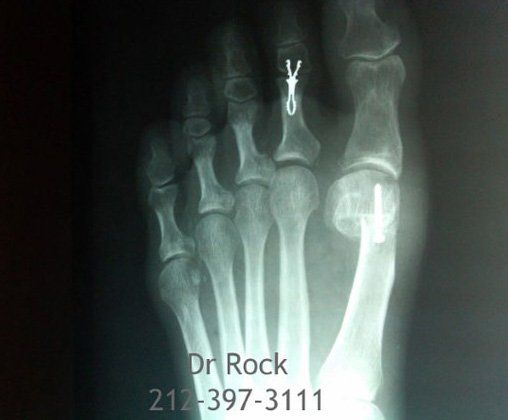

Take a look at our x-ray pictures of our recent footwork and see how your feet can benefit.

for more X-ray photos.